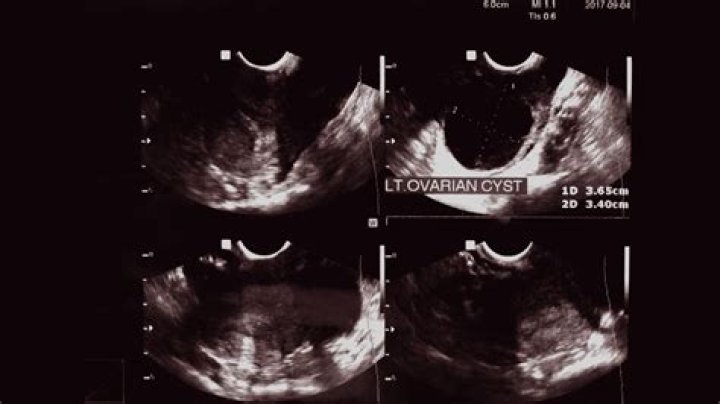

Are ovarian and breast cysts related?

A diagnosis of ovarian cysts is likely an indicator of hormonal milieu and thus may be related to breast cancer risk. Recent studies have reported an inverse relationship between prior ovarian cyst diagnosis and breast cancer risk.

How do you detect ovarian cysts?

Ovarian cysts

1. Physical exam. A doctor may feel a cyst during a pelvic exam.

2. Ultrasound. An ultrasound can pinpoint the location, size, and makeup of ovarian cysts. ...

3. Blood tests. If you are past menopause or at increased risk for ovarian cancer, your doctor may order CA-125 testing along with other diagnostic studies.